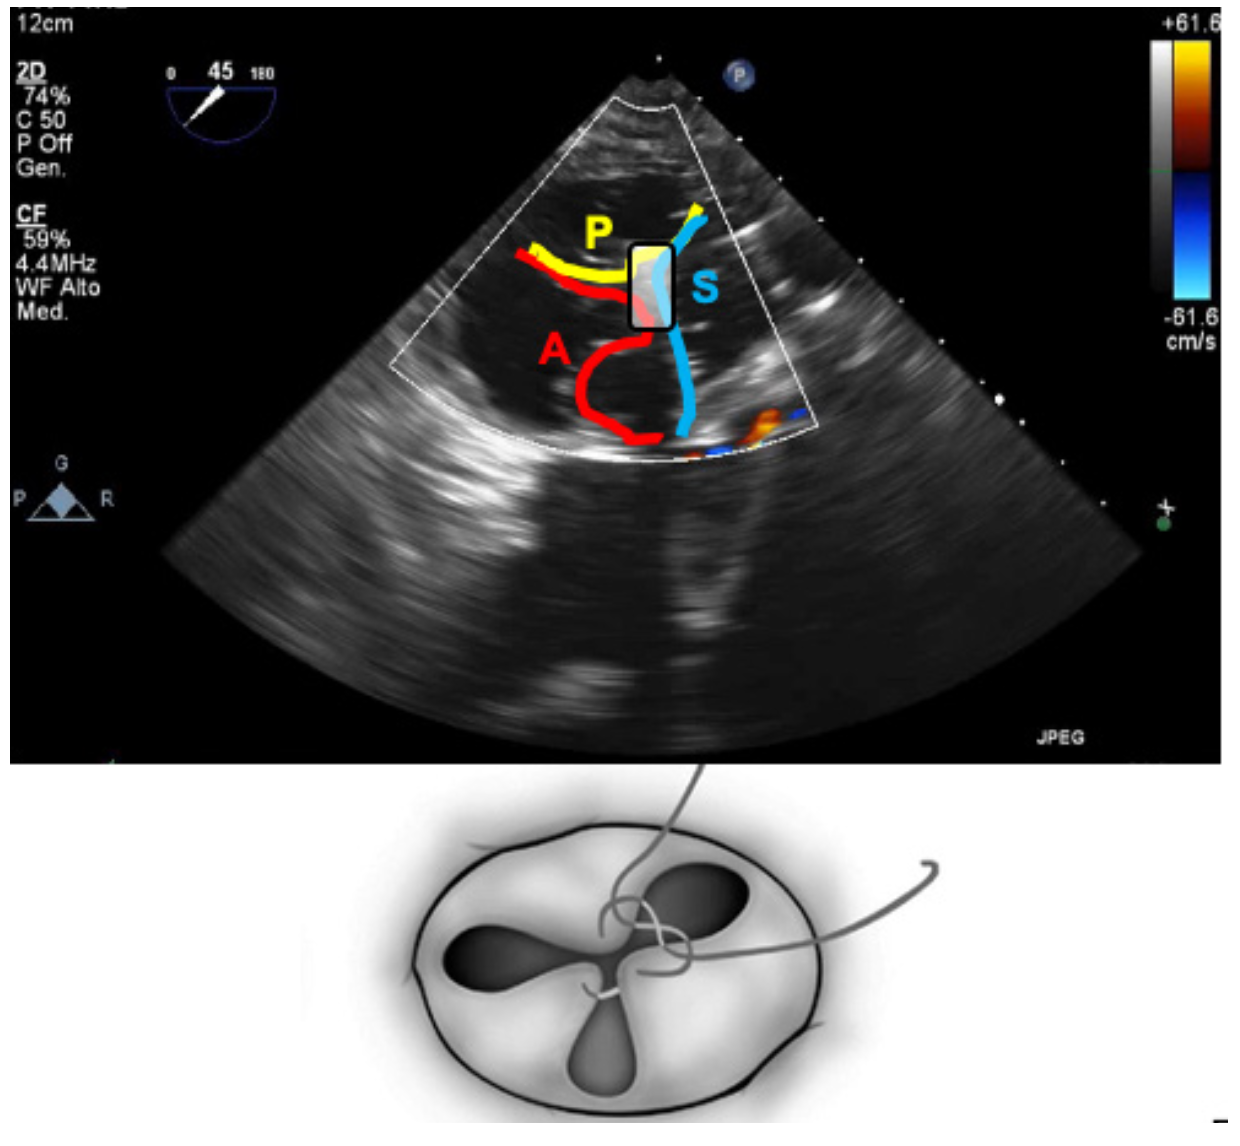

Under transesophageal echocardiography guidance, we attempted to grasp the anterior and septal leaflets. However, grasping was not initially successful. The clip was moved and deployed centrally, spanning the septal leaflet on one side and anterior and posterior leaflets close to the anteroposterior commissure on the other (Figure 1). Tissue grasping was checked and confirmed. Excellent final result was obtained with triple orifice creation (Figure 2) and mild residual regurgitation (Video Series).